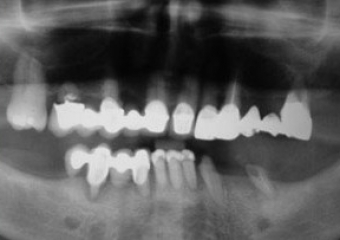

Raio X inicial

Raio X de controle, realizado em Setembro de 2008

Raio X de controle, realizado em Março de 2012